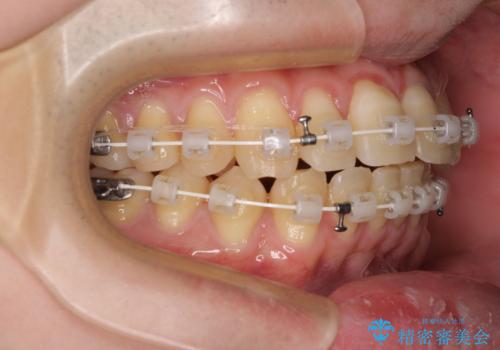

【モニター】前歯のデコボコとクロスバイト ワイヤー矯正で短期間に仕上げる

- 前歯のデコボコとクロスバイトを気にして来院された患者様です。

インビザラインでもワイヤー装置でも矯正治療は可能でしたが、煩わしい自己管理なしに短期間で治療を行いたいとのことで、目立たないワイヤー装置にて治療を行うこととしました。